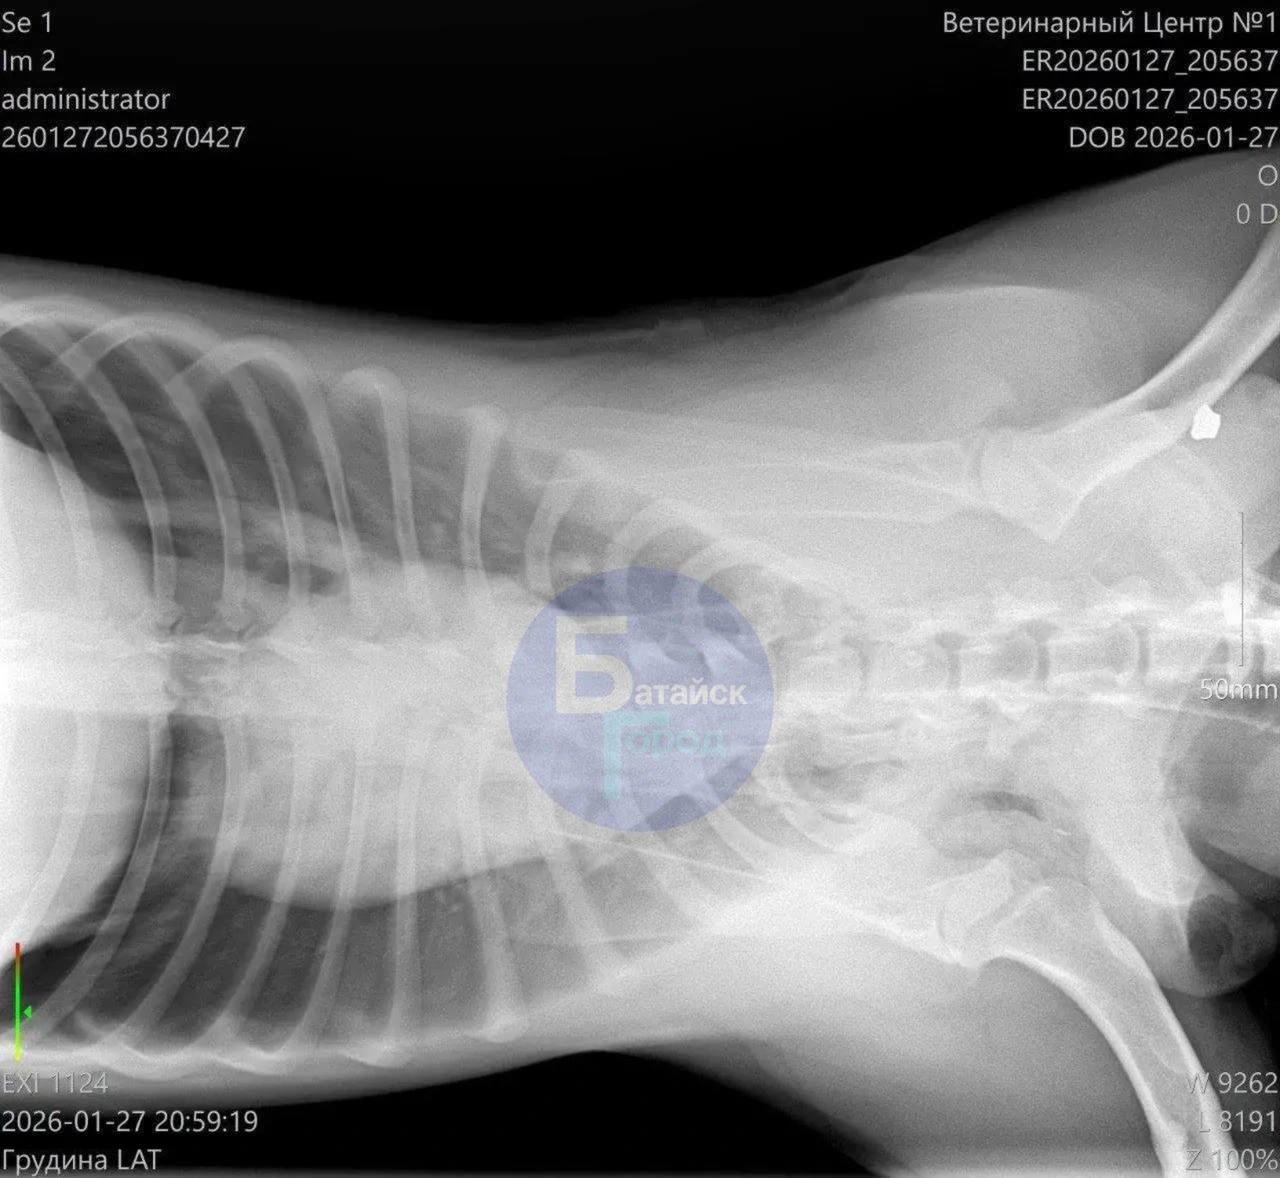

По сообщению, раненого пса обнаружили местные жители во время прогулки и отвезли в ветеринарную клинику, где животному экстренно пытались помочь. Спасти собаку не удалось — ветеринары не смогли восстановить работу сердца, пострадавшее от шока и кровопотери.